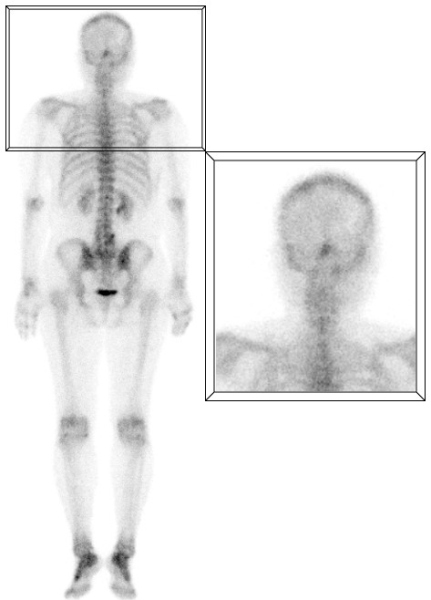

A) Captación difusa en huesos frontales

La hipercaptación difusa y simétrica en los huesos frontales suele ser secundaria a hiperostosis, definida como un crecimiento benigno excesivo de la tabla interna de los huesos frontales y, en algunos casos, parietales. Aunque se creía relacionada con trastornos hormonales, actualmente su etiología no está completamente clara. Se presenta en el 5 - 12% de la población, siendo más común en mujeres adultas mayores. Suele ser un hallazgo incidental sin significado patológico, aunque puede estar asociado a condiciones como diabetes, enfermedad tiroidea, virilismo y acromegalia, entre otras(1,2) (fig. 1).

B) Captación occipital en la línea media

Suele presentarse en la proyección de la protuberancia occipital externa, prominencia ósea donde se insertan el ligamento nucal y el músculo trapecio. Estos músculos prominentes expuestos a una alta sobrecarga constante pueden sufrir inflamación crónica y gradual, con la consecuente formación de exostosis por tracción, lo que explica el aumento focal de la captación en la gammagrafía ósea. Estudios recientes han demostrado la relación de este hallazgo con el uso de dispositivos electrónicos, especialmente en adolescentes y adultos jóvenes, que al asociarse a periodos prolongados de hiperflexión del cuello puede originar sobrecarga de estas estructuras musculares(3) (fig. 2).